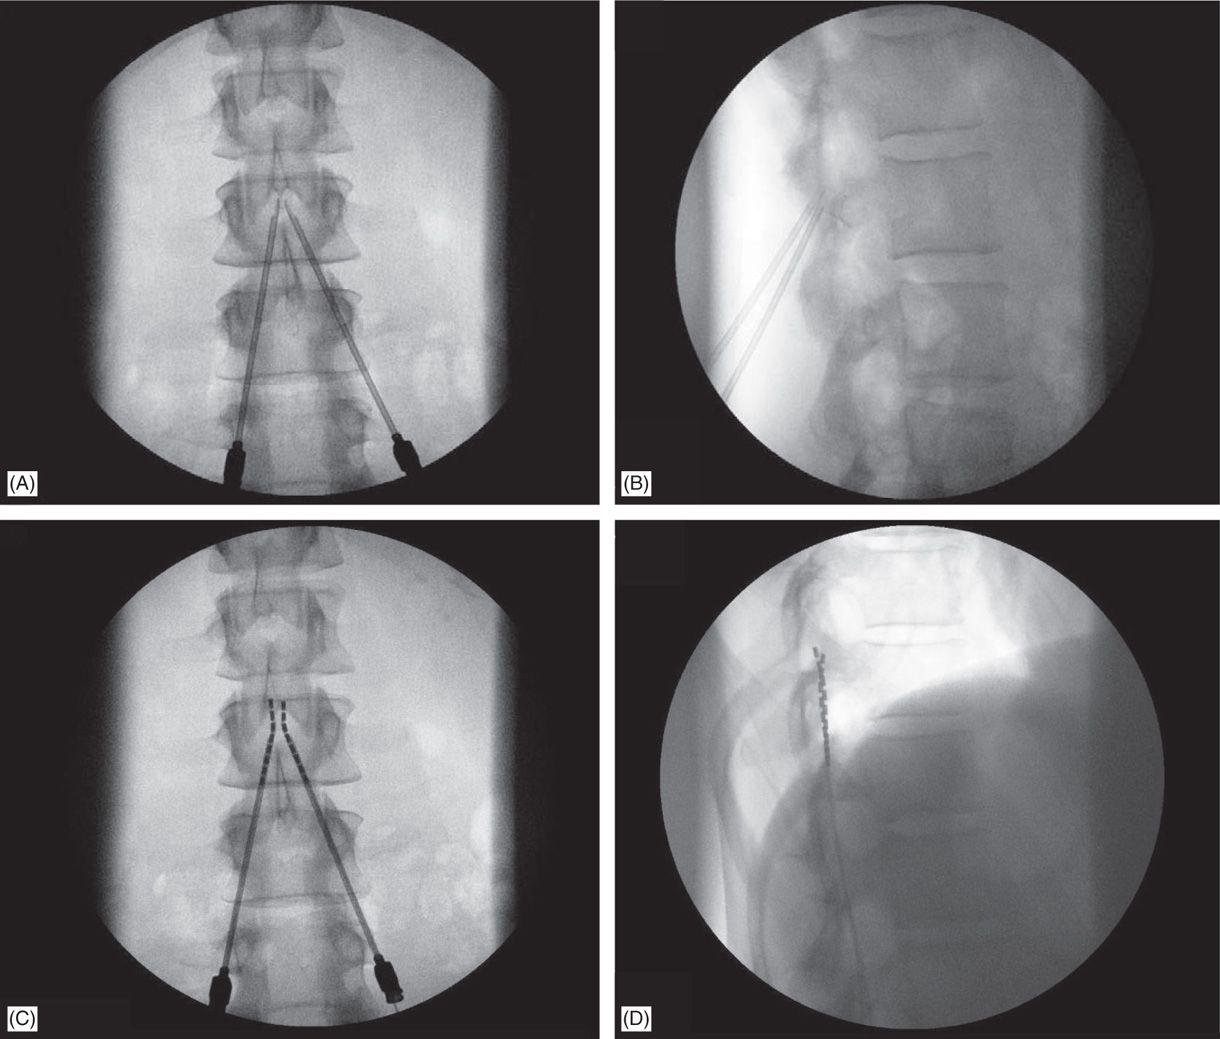

Radiographic position of the 10kHz spinal cord stimulator electrodes

Radiographic position of the 10kHz spinal cord stimulator electrodes Can You Have An X Ray With A Spinal Cord Stimulator The electrical signals block your nerves from feeling. Precision™ plus spinal cord stimulator system and precision novi™ spinal cord stimulator system. If you have either of these systems, you should not. Your doctor will provide you with a medical id card that authorizes and explains. The scs works by sending electrical signals to the nerves around your spine. In this. Can You Have An X Ray With A Spinal Cord Stimulator.